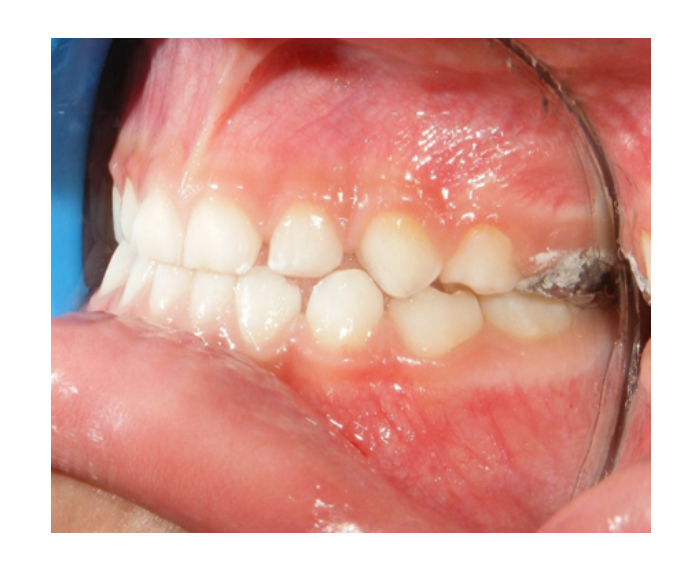

Clase I Protrusión

dental